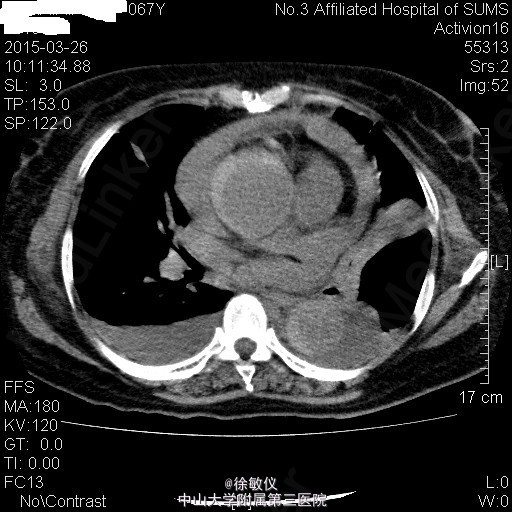

于急诊输液、止呕治疗后呕吐停止,胸闷持续3小时后症状减轻,予阿司匹林、氯吡格雷、立普妥负荷量口服后收入我科。 入院后查胸部、腹部ct发现有主动脉夹层。 诊断:冠状动脉粥样硬化性心脏病;主动脉夹层。

讨论:典型的急性主动脉夹层病人往往表现为突发的、剧烈的、胸背部、撕裂样疼痛。严重的可以出现心衰、晕厥、甚至突然死亡。该患者仅表现为胸闷,症状不典型。